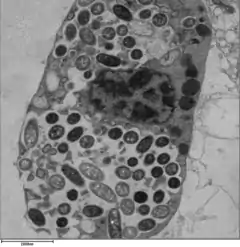

In humans, L. pneumophila invades and replicates inside macrophages. The internalization of the bacteria can be enhanced by the presence of antibody and complement, but is not absolutely required. Internalization of the bacteria appears to occur through phagocytosis. However, L. pneumophila is also capable of infecting non-phagocytic cells through an unknown mechanism. A rare form of phagocytosis known as coiling phagocytosis has been described for L. pneumophila, but this is not dependent on the Dot/Icm (intracellular multiplication/defect in organelle trafficking genes) bacterial secretion system and has been observed for other pathogens.[17] Once internalized, the bacteria surround themselves in a membrane-bound vacuole that does not fuse with lysosomes that would otherwise degrade the bacteria. In this protected compartment, the bacteria multiply.

Legionella-containing vacuole

For Legionella to survive within macrophages and protozoa, it must create a specialized compartment known as the Legionella-containing vacuole (LCV). Through the action of the Dot/Icm secretion system, the bacteria are able to prevent degradation by the normal endosomal trafficking pathway and instead replicate. Shortly after internalization, the bacteria specifically recruit endoplasmic reticulum-derived vesicles and mitochondria to the LCV while preventing the recruitment of endosomal markers such as Rab5a and Rab7a. Formation and maintenance of the vacuoles are crucial for pathogenesis; bacteria lacking the Dot/Icm secretion system are not pathogenic and cannot replicate within cells, while deletion of the Dot/Icm effector SdhA results in destabilization of the vacuolar membrane and no bacterial replication.[25][26]